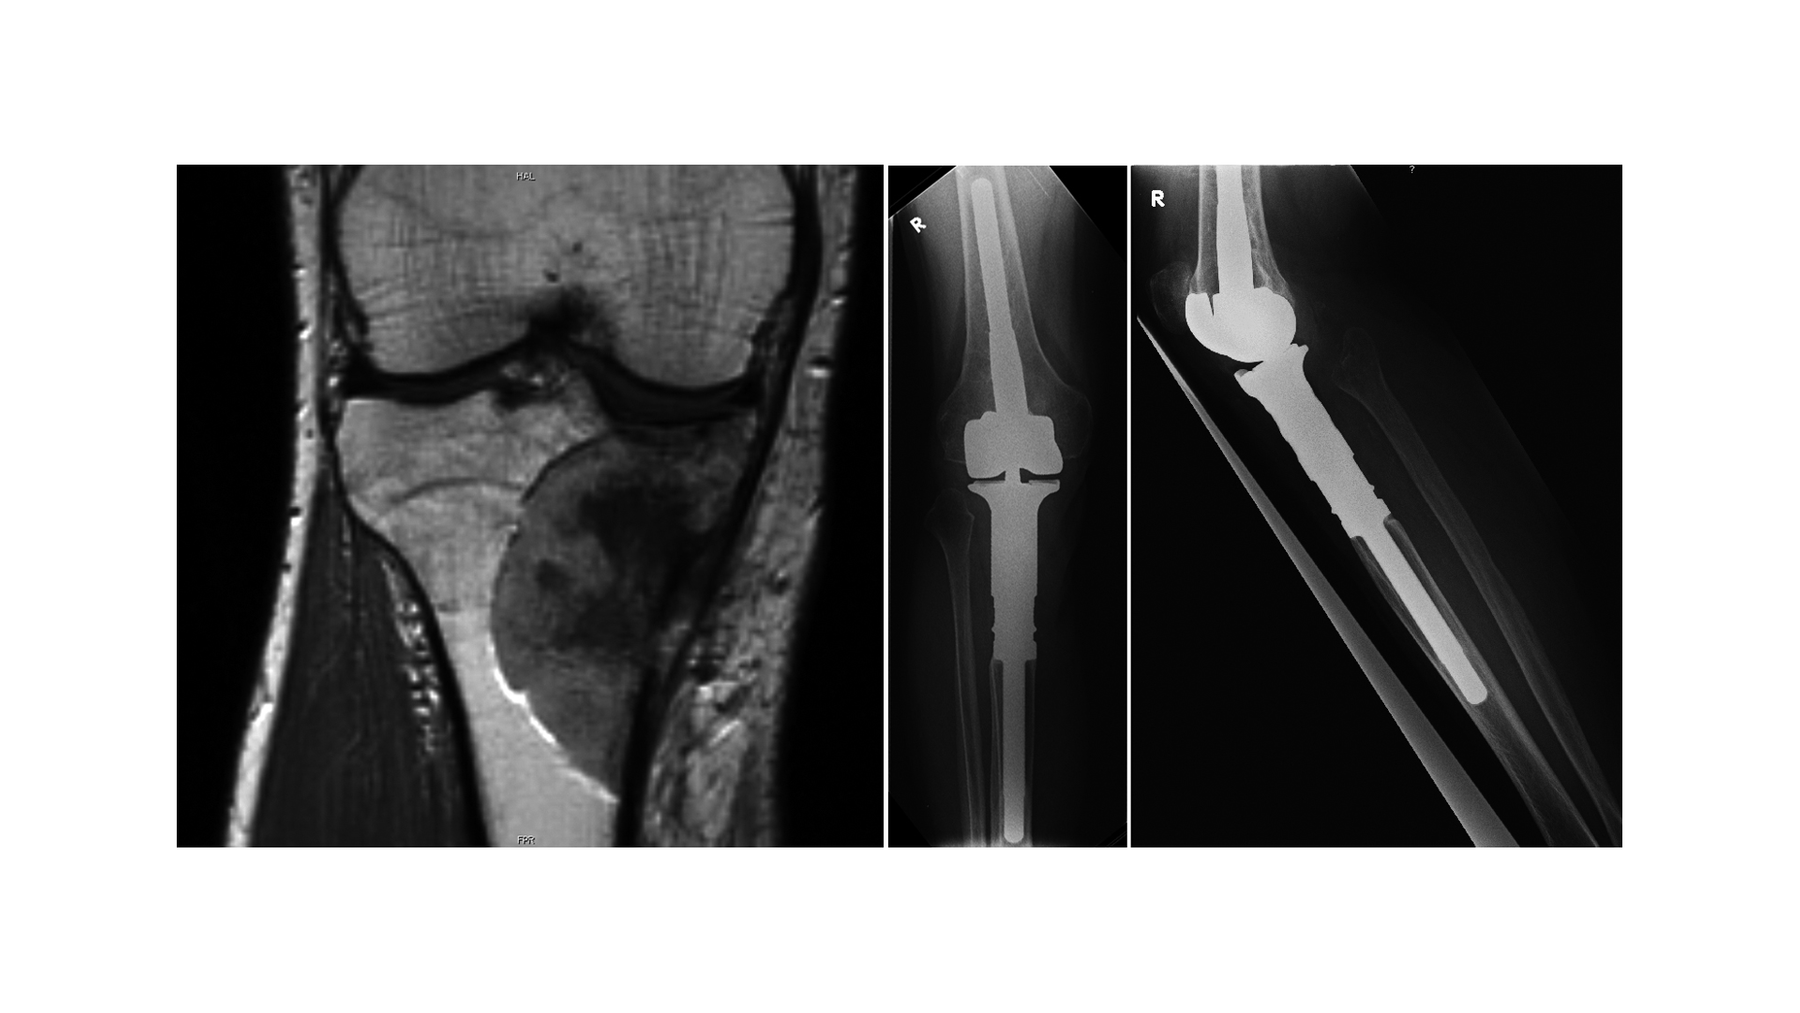

24-jährige Patientin mit periostealen Osteosarkom (G1) des distalen Femurs. Tumorprothese, 10-jähriger Verlauf.